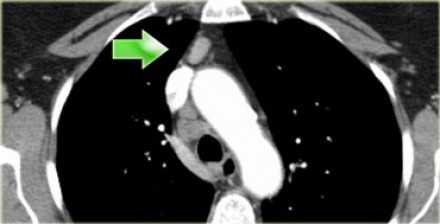

На ПЭТ изображении слева показано накопление 18Р-дезоксиглюкозы в узле 8 группы. На соответствующем КТ изображении видно что данный лимфатический узел (голубая стрелка) не увеличен. Вероятность того что в имеется метастатическое поражение данного узла чрезвычайно высока, поскольку специфичность ПЭТ выше чем измерение размеров лимфатических узлов.

![14]()